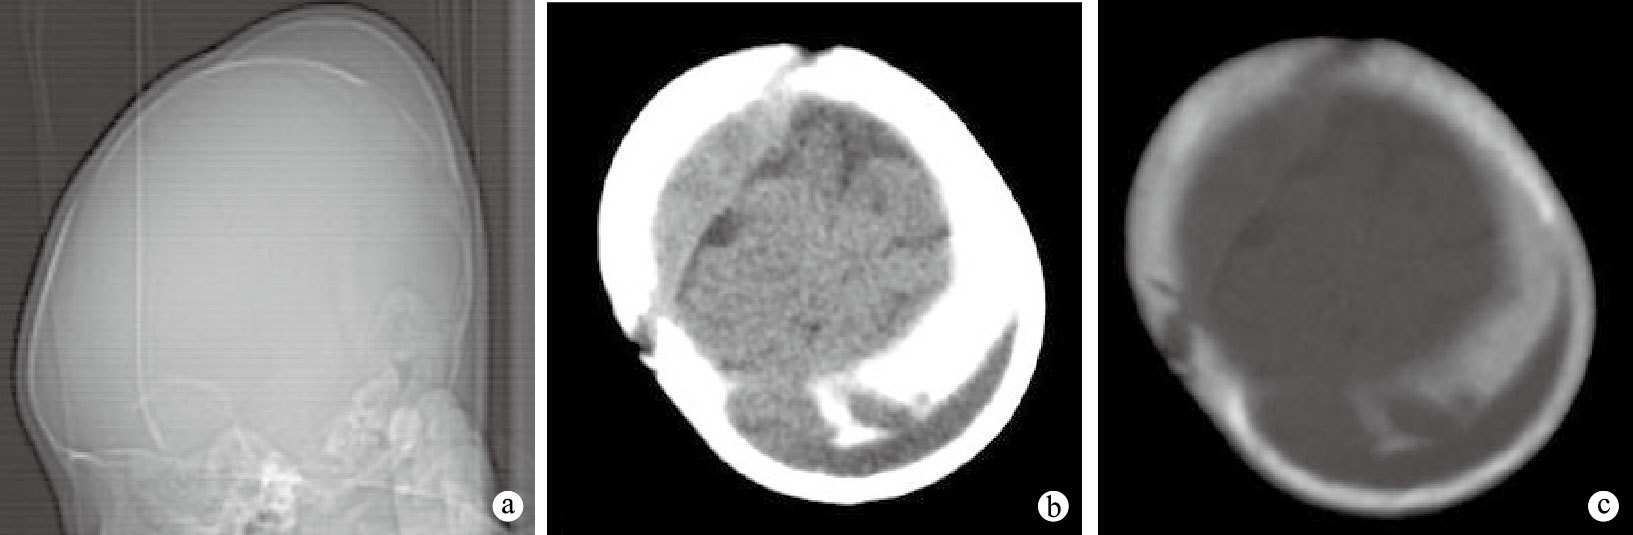

15例顱骨骨膜下血腫均為單個血腫,位于左或右側頂骨外表面,局限于一側頂骨范圍內,顱骨輕度下陷,骨質密度稍減低;骨膜下見新生弧形骨質密度影,內外邊緣光整,結構、密度、弧度與顱骨相似,血腫邊緣新生骨與顱骨外板相延續,鈍角相交,緊密連接,新生骨與顱骨間見新月形軟組織密度影,CT值17~27 HU,呈“夾心餅征”樣之雙層顱板表現;其中3例大小與頂骨相當的血腫下顱骨內外板及板障全層骨質部分吸收消失;顱內腦實質及腦溝、池未見明顯異常改變。典型病例頭顱CT圖像見圖 1。

a.頭顱側位示頂部新生骨丘狀隆起,后頂部顱骨骨質密度稍減低,少部分缺失 b.頂部斷層腦組織窗,左頂部新生骨與顱骨間見新月形稍低密度影,CT值17 HU,腦實質及腦溝、池未見明顯異常改變 c.頂部斷層骨窗,左側頂骨輕度下陷,骨質密度稍減低,部分內外板及板障全層骨質吸收消失;頭皮下見新生弧形骨質密度影,內外邊緣光整,結構、密度、弧度與顱骨相似,厚度均勻,邊緣與顱骨外板相延續,緊密連接;新生骨與顱骨間見新月形間隙,呈“夾心餅征”樣之雙層顱板表現